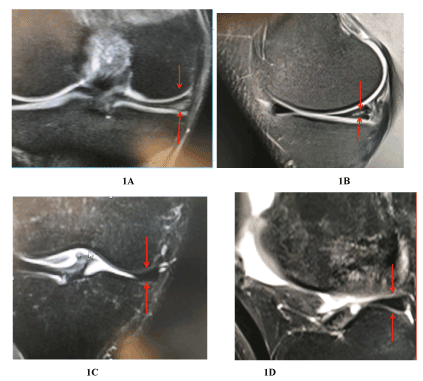

Figure 1. (A, B, C and D) A gradient-echo T2-weighted coronal image demonstrates tear of the body and posterior horn of the medial meniscus, extending to the inferior articular surface, with horizontal orientation of the cleavage. Three months post injection of chondrocytes demonstrate complete resolution of the signal intensity and meniscal shape